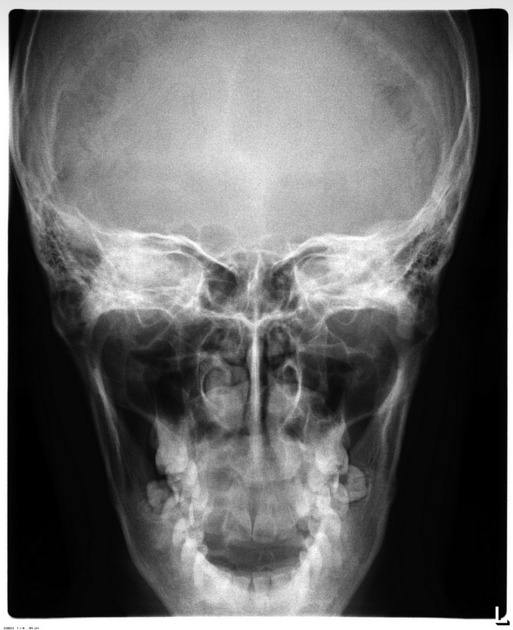

What is the Waters or Occipito-Menton projection?

canthomeatal plane forms 37 angle with image receptor, pt faces receptor

What does the waters projection give insight to?

Sinuses, cheek bones, septum and mandible